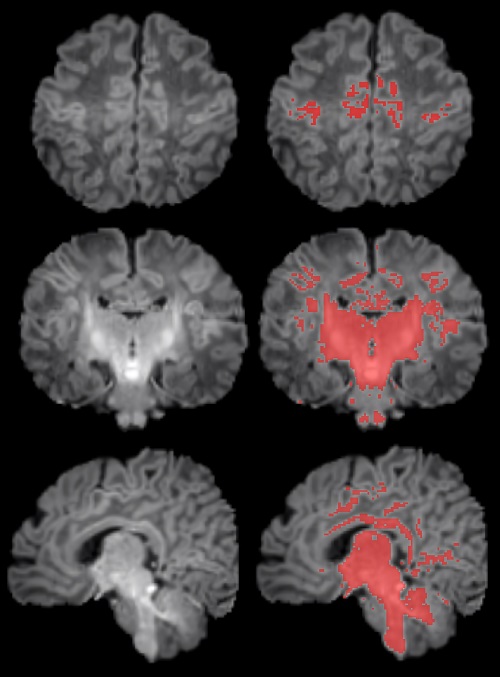

Para llevar a cabo el estudio se reclutó a mujeres embarazadas en seguimiento en el Hospital Clínic Barcelona, el Hospital de Sant Pau y el Hospital Sant Joan de Déu. Se monitorizaron los niveles de contaminantes atmosféricos a los cuales estaban expuestos durante la gestación y, después del parto, se seleccionó a 132 recién nacidos. A estos se les realizó una resonancia magnética antes de cumplir el primer mes de vida para observar el grado de maduración cerebral según sus niveles de mielinización.

Los resultados muestran una correlación clara entre una mayor exposición materna a PM2.5 durante el embarazo y una menor mielinización en el cerebro de los recién nacidos. "La contaminación atmosférica, concretamente las PM2.5, se asocia con una alteración en el proceso de mielinización, un mecanismo esencial de maduración cerebral. Por ello hay que continuar controlando la contaminación y estudiar cómo esta ralentización puede influir en el desarrollo posterior del cerebro de los niños y niñas", expresa Martínez-Vilavella. El trabajo también indica que este efecto responde a la combinación de los diferentes elementos que forman las PM2.5, sin que se pueda identificar un único elemento como responsable.